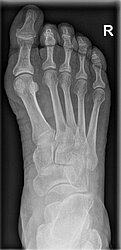

Der Hallux valgus ist eine Deformität des Vorfußes, bei der die Mittelfußköpfchen auseinanderweichen. Dabei verschiebt sich insbesondere das erste Mittelfußköpfchen in Richtung Körpermitte, während der Großzeh gleichzeitig nach außen abweicht. Das führt zu einer Insuffizienz des Bandapparates im Vorfuß und der typischen Hallux valgus-Fehlstellung. Diese geht vor allem mit belastungsabhängigen Schmerzen, Druckstellen und Problemen bei der Schuhversorgung einher. Ursachen für den Hallux valgus können unter anderem angeborene Faktoren sowie falsches, einengendes Schuhwerk oder Fehlbelastungen sein.

Um festzustellen, ob eine Hallux valgus-Deformität vorliegt, erfolgen zunächst ein Anamnesegespräch sowie eine ausführliche Untersuchung beider Füße in stehender Position. Häufig ist die Erkrankung dabei schon deutlich zu erkennen. Zur Planung der Therapie kommen darüber hinaus Röntgenaufnahmen des betroffenen Fußes zum Einsatz. Eine Schnittbilddiagnostik (CT, MRT) ist in der Regel nicht erforderlich.